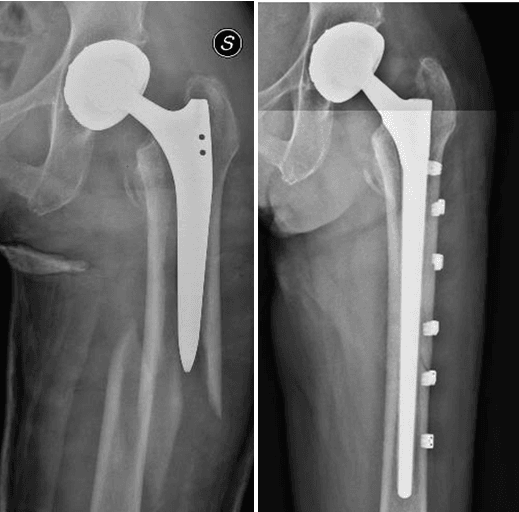

L’intervento chirurgico di revisione protesica si attua nel caso di fallimento dell’impianto primario. La revisione può essere totale (quando vengono sostituite tutte le componenti) o parziale (quando vengono sostituite solo alcune componenti), a seconda dell’entità e del tipo di problema riscontrato.

- Frattura peri-protesica

La revisione protesica rappresenta una vera e propria sfida per il Chirurgo Ortopedico, soprattutto in quei casi gravati da importante perdita del bone stock, da deficit dei tessuti molli periarticolari o in presenza di alterazioni del trofismo cutaneo, talvolta con perdita severa di sostanza, in esiti di plurimi interventi chirurgici.

Grazie ad un’esperienza chirurgica decennale nel trattamento e nella gestione di casi difficili di revisione protesica, presso il nostro centro di Chirurgia Protesica pianifichiamo accuratamente gli interventi ricostruttivi protesici, avvalendoci delle più innovative tecniche e metodiche chirurgiche (impianti protesici su misura quando necessari), ponendo particolare attenzione nell’utilizzo di materiali protesici biocompatibili che garantiscono un’ottimale osteointegrazione ed una resistenza all’usura sempre maggiore.